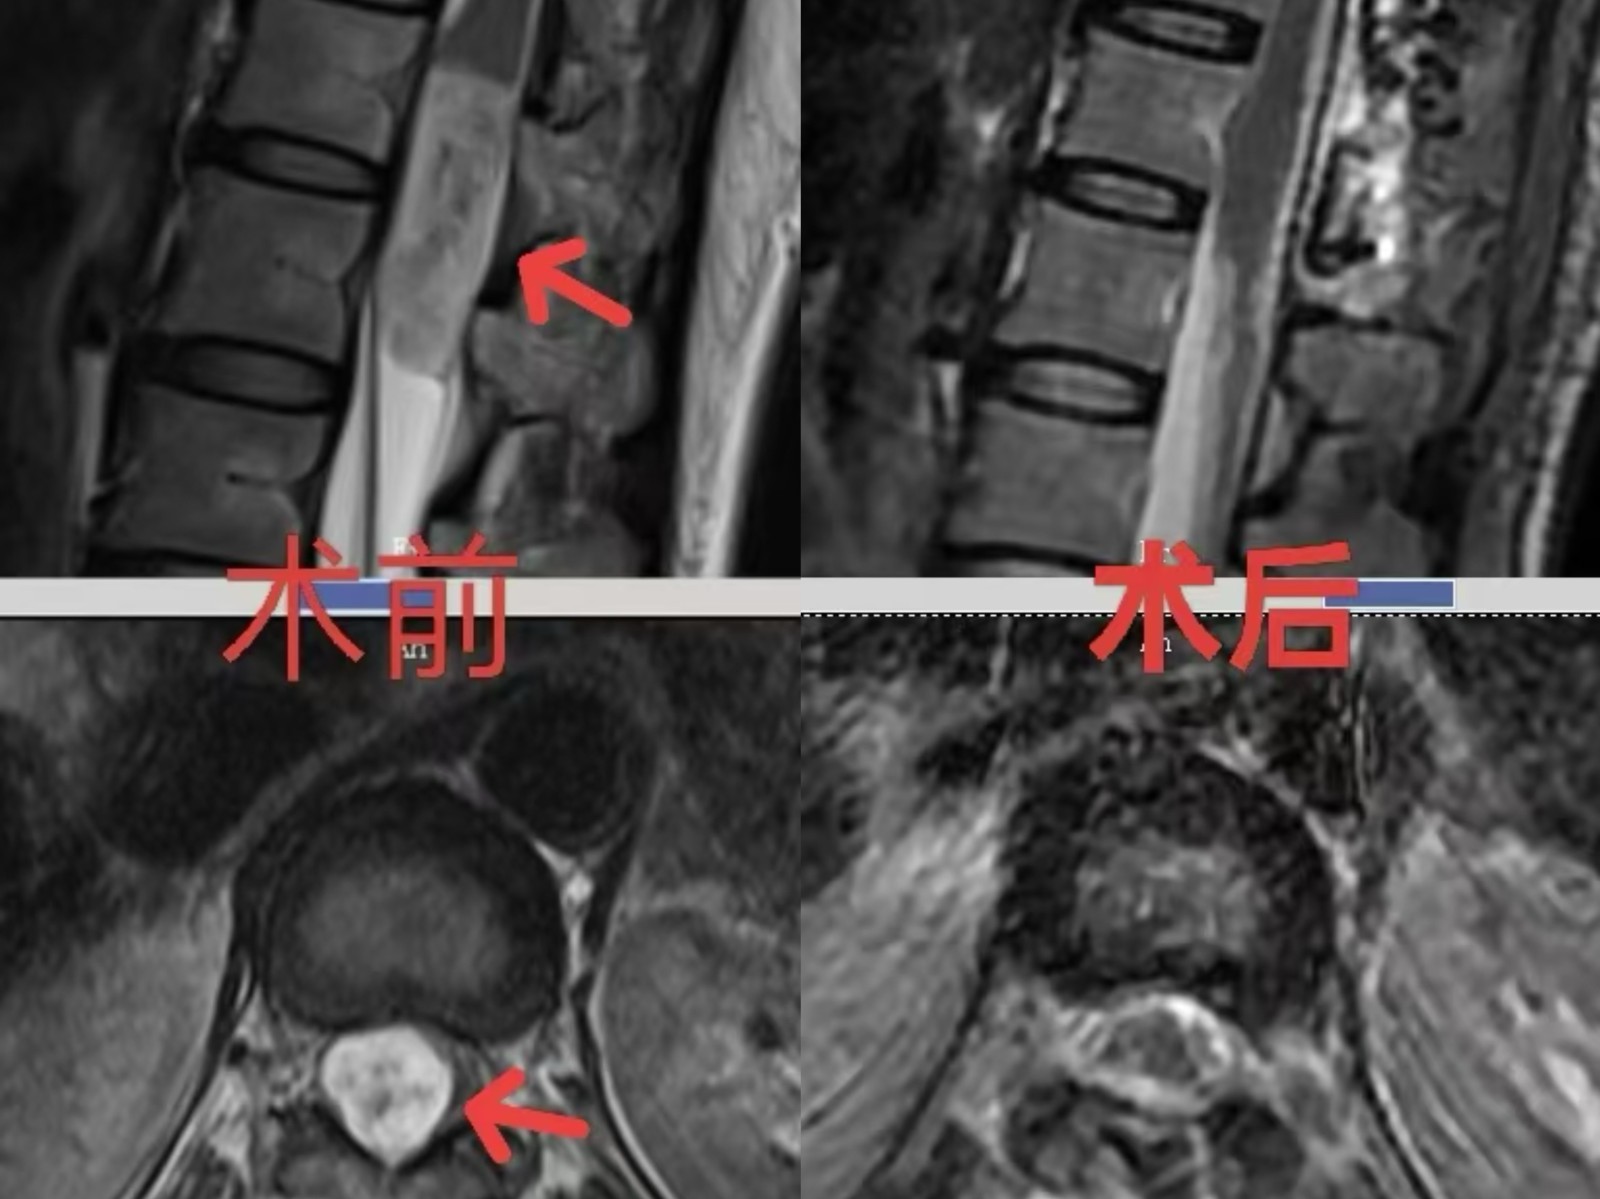

40歲的曹女士一個多月前開始腰痛,并向右臀、右大腿外側放射,呈酸脹痛。彎腰、起身困難,伴腰部畏寒、雙下肢發(fā)涼,嚴重影響生活,且痛苦不堪。自行貼膏藥無效后,在中醫(yī)科按“腰椎間盤突出伴坐骨神經(jīng)痛”收治,治療效果不佳。磁共振檢查揭示真相:椎管內(nèi)腫瘤!正是這個腫瘤壓迫脊髓,導致了她的癥狀。曹女士來到十堰市人民醫(yī)院神經(jīng)外科二病區(qū),羅俊杰主任團隊評估后指出:腫瘤壓迫脊髓圓錐,正常結構成一小片狀,須盡快切除!否則持續(xù)壓迫加劇痛苦不說,隨即而來的很可能就是雙下肢癱瘓、大小便失禁等嚴重后果,且拖延將顯著增加手術難度、影響康復。

脊髓結構最粗的地方僅僅像我們的手指,該腫瘤大小約4厘米*1.5厘米,已經(jīng)接近正常結構大小,脊髓圓錐受壓嚴重,被壓成了一個薄薄的片狀。腫瘤深藏腰椎椎管內(nèi),被脊髓、神經(jīng)根、緊密包繞。手術猶如在神經(jīng)與血管的“雷區(qū)”中拆彈,稍有不慎即可導致不可逆的損傷,對手術團隊技術要求極高。

經(jīng)周密術前準備,神經(jīng)外科二病區(qū)羅俊杰主任團隊為曹女士實施了椎管腫瘤切除術。術中發(fā)現(xiàn)腫瘤與圓錐處粘連嚴重。在顯微鏡下,靠著醫(yī)生的耐心與精湛的技術,一點一點地將腫瘤分離,手術歷時5個多小時,最終將腫瘤全切,并且正常結構得以完全保護。

術后,曹女士即刻感覺疼痛消失,無力感明顯改善。經(jīng)過神經(jīng)外科醫(yī)護人員的精心治療與康復,術后兩周,曹女士痊愈出院,擺脫長達一個多月的劇痛折磨。出院前,她滿懷感激地為神經(jīng)外科二病區(qū)團隊寫下感謝信,將錦旗贈予醫(yī)護團隊,臉上重現(xiàn)久違的笑容。